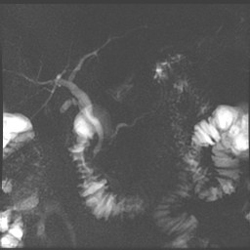

Imaging of pancreatic divisum with a subtle pancreatic duct stricture in the head and neck

Pancreatic divisum, as imaged by magnetic resonance cholangiopancreatography (MRCP)